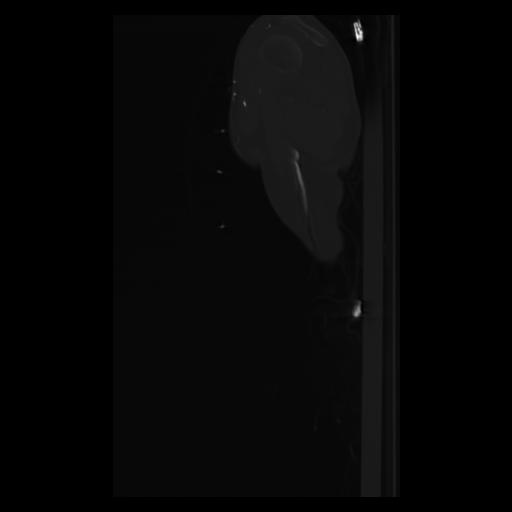

30 CUERPO,CE,Sagittal,3.000,CUERPO,Sagittal,